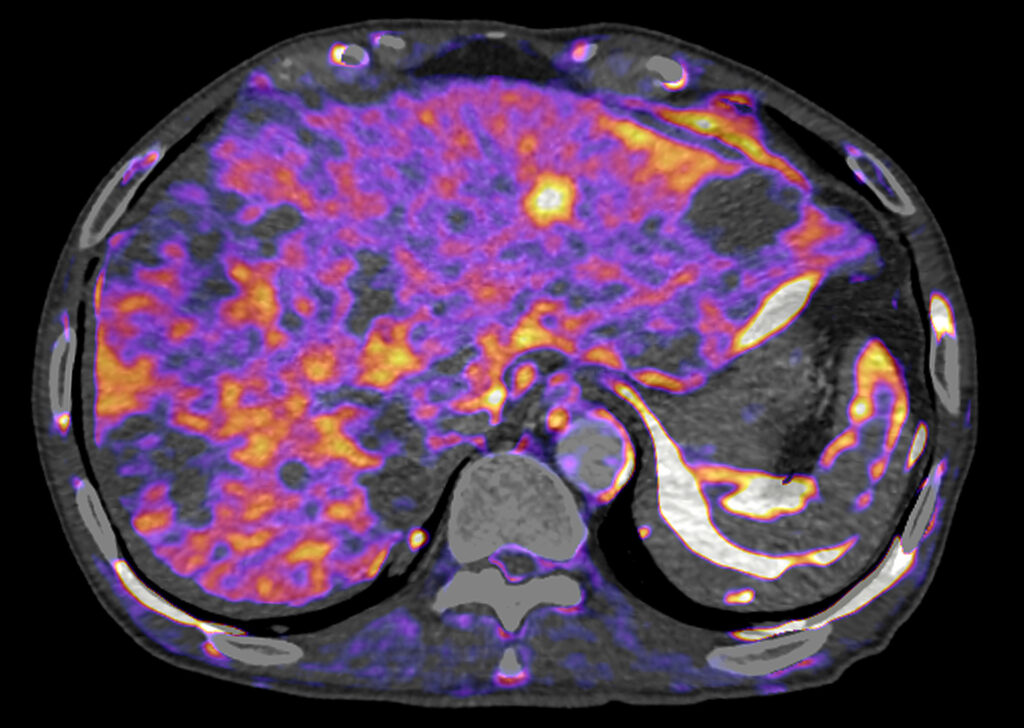

CT Body Perfusion 4D

CT Body Perfusion 4D enables whole organ functional assessment. Parametric maps, based on the contrast flow through an organ, provide additional information to aid clinical decision-making.